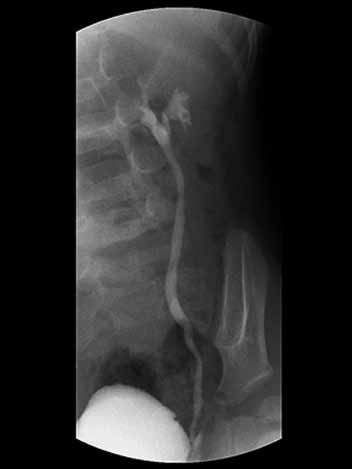

Menina de quatro anos, em investigação diagnóstica para refluxo vesicoureteral, realizou uretrocistografia miccional, conforme imagem a seguir:

Com base na imagem apresentada, a graduação de refluxo vesicoureteral de acordo com o sistema internacional proposto pelo International Reflux Study Group (IRSG) é